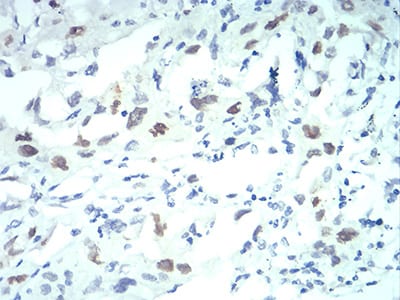

Immunohistochemical analysis of paraffin-embedded human lung cancer tissues using KPNA2 mouse mAb with DAB staining.